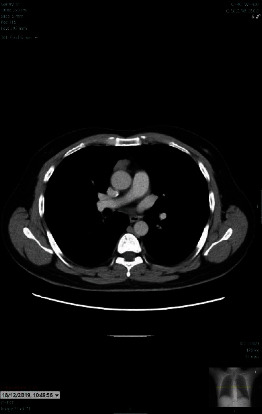

This case report presents a unique clinical scenario of a 58-year-old male suffering from severe refractory myasthenia gravis and concurrent alopecia areata postthymectomy. Myasthenia gravis, a common autoimmune disorder, is characterized by muscle weakness due to autoantibodies targeting neuromuscular junction proteins. Alopecia areata, another autoimmune disease, is often seen in individuals with myasthenia gravis, suggesting a shared immunological basis. The patient's condition was resistant to conventional treatment, and he developed alopecia areata following thymectomy. Despite the challenges in managing refractory myasthenia gravis and the associated alopecia areata, significant improvements were observed following a cortisone taper. This case highlights the potential therapeutic role of cortisone tapering in managing refractory myasthenia gravis and associated alopecia areata. This case also prompts further exploration into the immunological shifts following thymectomy, particularly its potential role in triggering alopecia areata.